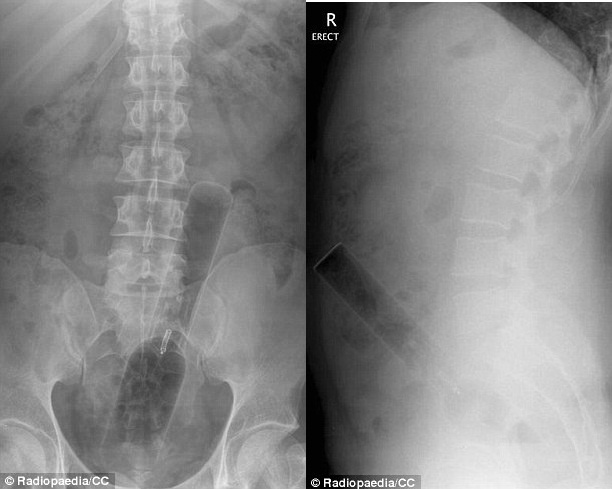

| Lọ cà phê nhỏ mắc kẹt trong cơ thể bệnh nhân. |

| Đồ chơi tình dục tự chế từ vỏ tuýp vitamin Berocca mắc kẹt trong trực tràng của một bệnh nhân nam. |